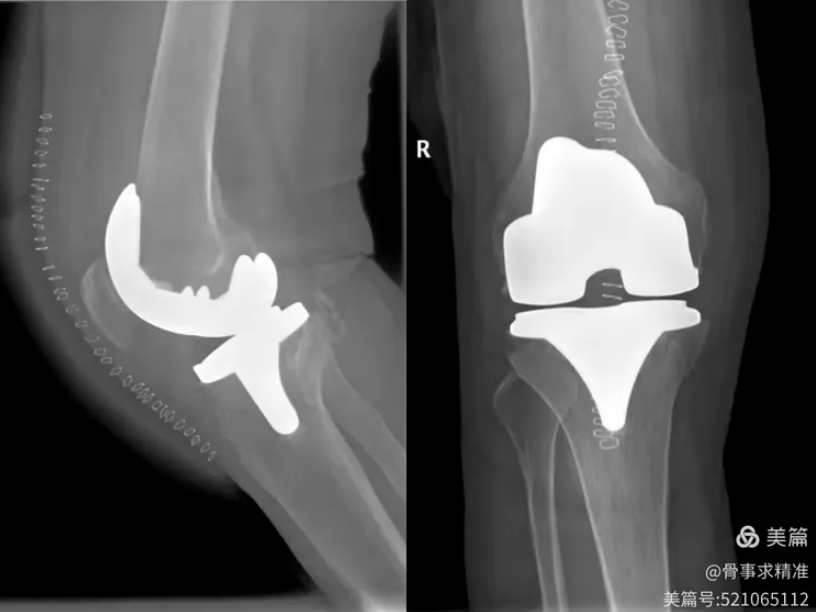

机器人系统在辅助全膝关节置换中,通过术前三维重建与个体化规划,实现不开髓、数据化精准截骨,最大限度保留骨量,创伤更小、出血更少、疼痛更轻、恢复更快。术中假体位置、角度、旋转对位全程精准控制,大幅度降低人为误差,提升手术安全性。

膝关节术后片